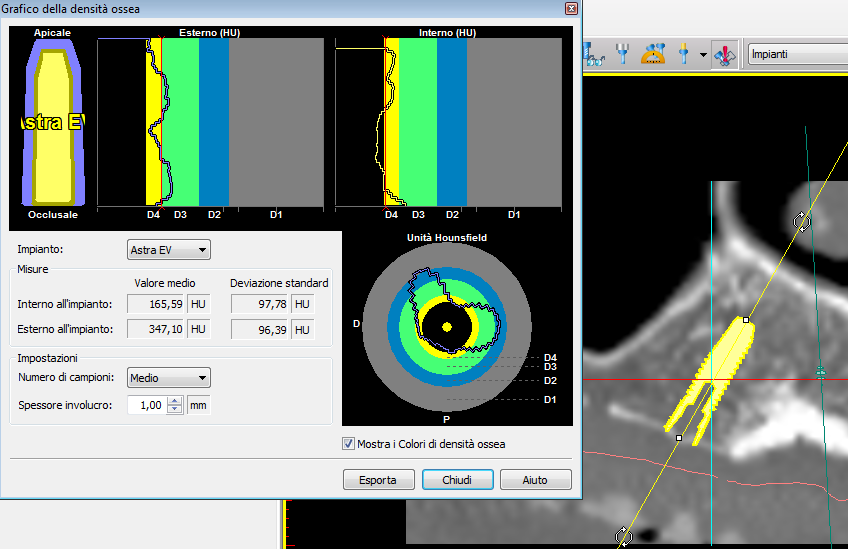

La nuova protesi totale provvisoria ha portato immediatamente un miglioramento funzionale ed estetico, con un notevole beneficio psicologico sulla paziente ed un enorme vantaggio per il prosieguo della terapia (Figg. 8-10). Il nuovo montaggio con denti di maggiori dimensioni ed una differente occlusione ha conferito un miglior supporto al labbro superiore ed una migliorata estetica del sorriso (Fig. 11). Alla luce della nuova situazione, accettata e gradita dalla paziente, si è incominciato a pianificare la procedura chirurgica. Avendo la CBCT evidenziato dei volumi ossei adeguati (Fig. 12), si è proceduto allo studio del caso mediante un software di chirurgia guidata (Simplant, Dentsply-Sirona) (Figg. 13, 14).

Una delle peculiarità del software Simplant è di fornire dettagliate informazioni riguardanti la qualità dell’osso alveolare nelle aree selezionate per l’intervento implantare, agevolando e semplificando così il lavoro del professionista. Con la suddetta funzione infatti, il clinico potrà selezionare il sito più corretto per il posizionamento delle fixtures, sfruttando la miglior qualità ossea messa in risalto dalla diversa colorazione del programma (Fig. 14). Il vantaggio della funzione del software Simplant diventa di strategica importanza in quei casi in cui si decidesse di optare per una chirurgia con carico immediato degli impianti.

La pianificazione con Simplant permette l’accoppiamento tra la protesi e i tessuti molli oltre alla corretta valutazione della posizione, dell’inclinazione e dell’orientamento tridimensionale degli impianti (Figg. 15-17). Questo tipo di progettazione consente di eseguire una procedura chirurgica protesicamente guidata, sfruttando l’emergenza degli impianti nella loro più ideale posizione, con benefici dal punto di vista protesico e biomeccanico (Figg. 18, 19)